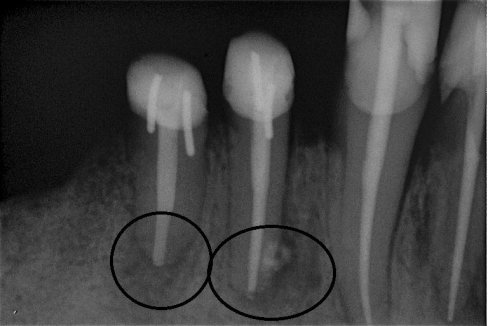

Fallbeispiel für eine große Entzündung an der Wurzel

Wurzel nach erfolgreicher Behandlung 2 Monate später schon fast ausgeheilt

Fallbeispiel für eine unvollständige Wurzelfüllung

nach Revision und dichtem Verschluss